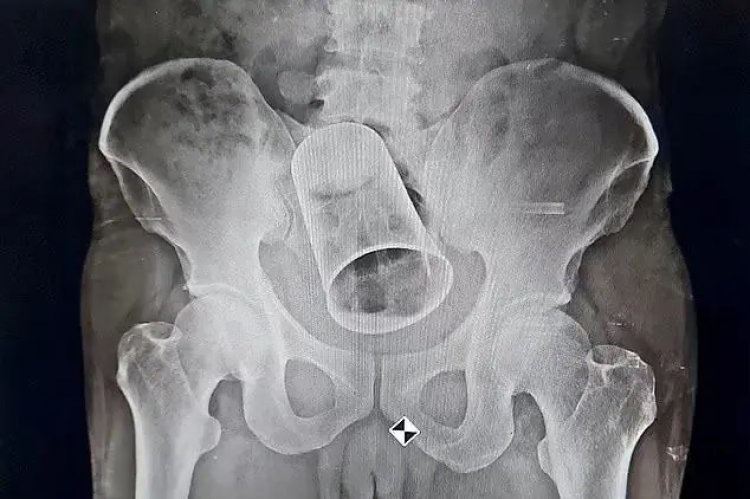

O homem estava bebendo com os amigos em Surat, em Gujarat, Estado onde o consumo de álcool é proibido. Após ficar embriagado, os “amigos” enfiaram um copo de 8 centímetros de diâmetro e 15 centímetros de comprimento.

Entretanto, um exame de raio-X revelou o objeto. O homem foi internado em um hospital. Ele passou por cirurgia e teve o objeto removido.